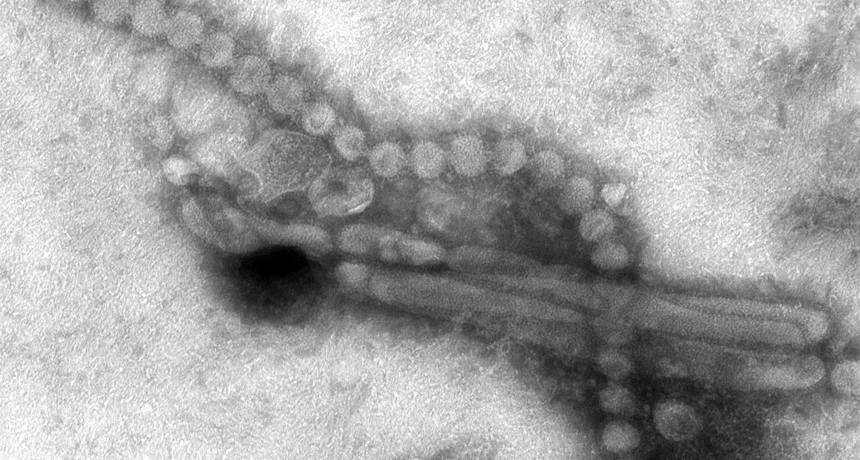

The H7N9 flu virus (shown) has the potential to become a pandemic, scientists say.

Cynthia S. Goldsmith and Thomas Rowe/CDC